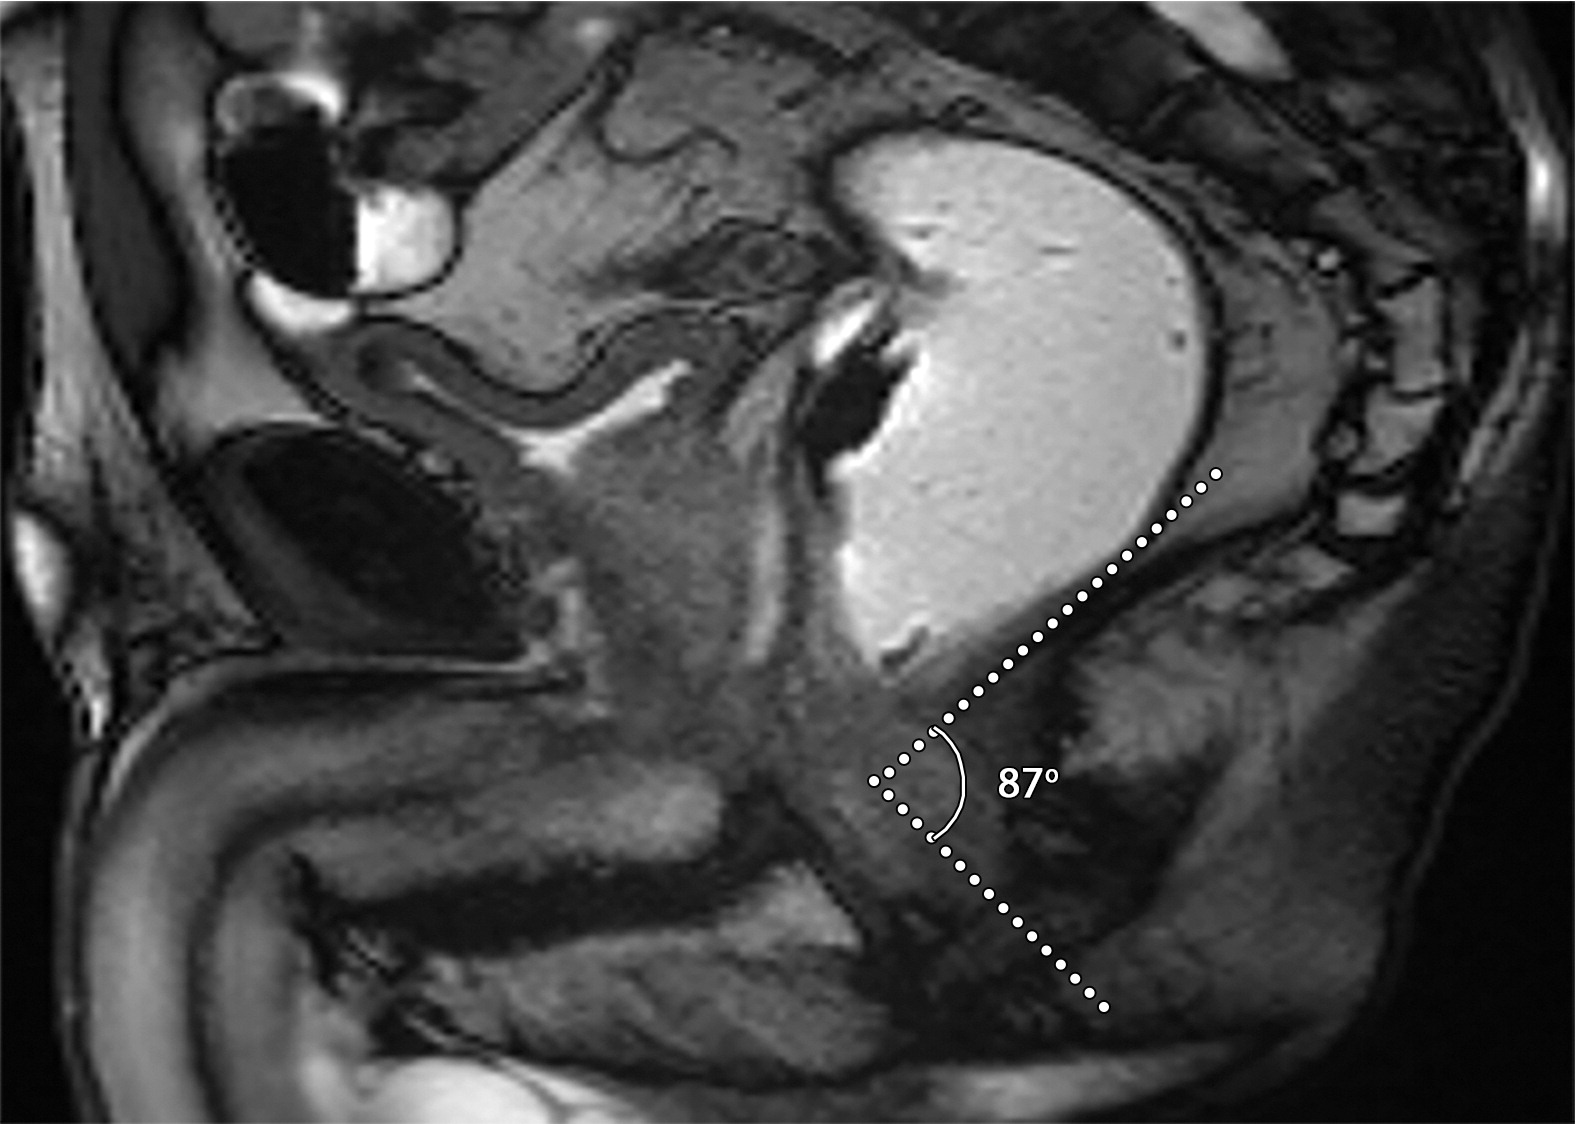

耻骨前列腺和前列腺尿道角

患者男性,39岁,良性前列腺增生,骶正中线TrueFISP MR图像显示,耻骨前列腺角从静息时的42°(a)正常增加到用力时的91°(b)。(c)67岁男性的矢状位T2加权MR图像显示前列腺-尿道角测量值为66°。